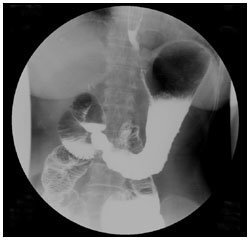

日々の症例 102 胃腫瘍 102 1 60歳代 男性 上腹部痛 画像所見 Ugi 腹臥位充満像で胃体下部大弯を中心に10cm以上の範囲で脳回状のfilling Defectがみられる 進行胃癌にみられるような硬さはなく 胃壁の進展性も比較的保たれている Ct